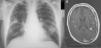

Physical examination showed fever 37.9°C, blood pressure 135/78mmHg, breathing rate 28 breaths/minute and heart rate 103 beats/minute, with bilateral fine crackles on lung auscultation. Blood test results showed 16600 leukocytes, 303000 platelets, and normal serum biochemistry (including liver function tests and procalcitonin), with the exception of C-reactive protein 5.7mg/dl. Baseline arterial blood gases were pO2 63mmHg, pCO2 36mmHg, pH 7.43 and oxyhemoglobin saturation 91%. Standard posteroanterior chest X-ray revealed cavitated alveolar infiltrate in the right upper lobe and infiltrate without cavitation in the left lower lobe (Fig. 1A).

Two blood cultures were performed, in aerobic and anaerobic media, and empirical treatment was started with piperacillin-tazobactam. Urine was negative for pneumococcal and Legionella antigens. After 4 days of antibiotic treatment without improvement, a chest–abdomen CT was performed, confirming previous radiological findings, with no other changes. Rhodococcus equi was isolated from both blood cultures, so based on susceptibility test results treatment was switched to imipenem, rifampicin and gentamicin. After 10 days of hospitalization, the patient began to complain of headache and instability, so magnetic resonance imaging (MRI) of the head was performed (Fig. 1B), revealing 8 cortical-subcortical nodular lesions, less than 1cm in size, indicative of brain abscesses.